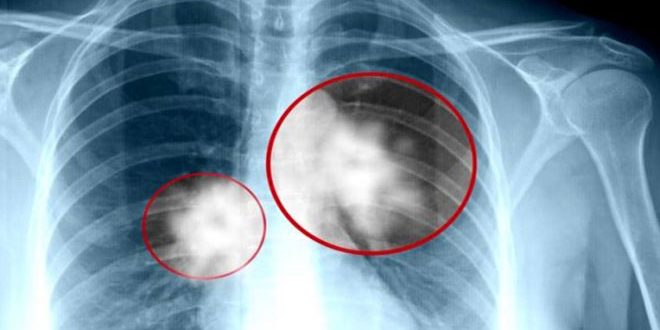

توصل باحثون صينيون إلى طريقة جديدة في علاج نوع شائع من سرطان الرئة وذلك بمكافحة الجين الذي يؤدي إلى هذا النوع من السرطانات.

ووفقا للدراسة التي أجراها باحثون من معهد خفي للعلوم الفيزيائية التابع للأكاديمية الصينية للعلوم فإن للجين /إم إم بي 11/ دورا في التسبب بسرطان الغدة الرئوية النوع الأكثر شيوعا من سرطان الرئة حيث تبينت زيادة تمثيله في كل من أنظمة الأنسجة والأمصال عند المصابين بالسرطان إثر دوره الرئيسي في تعزيز الانتشار والانتقال والغزو لخلايا الورم السرطاني.